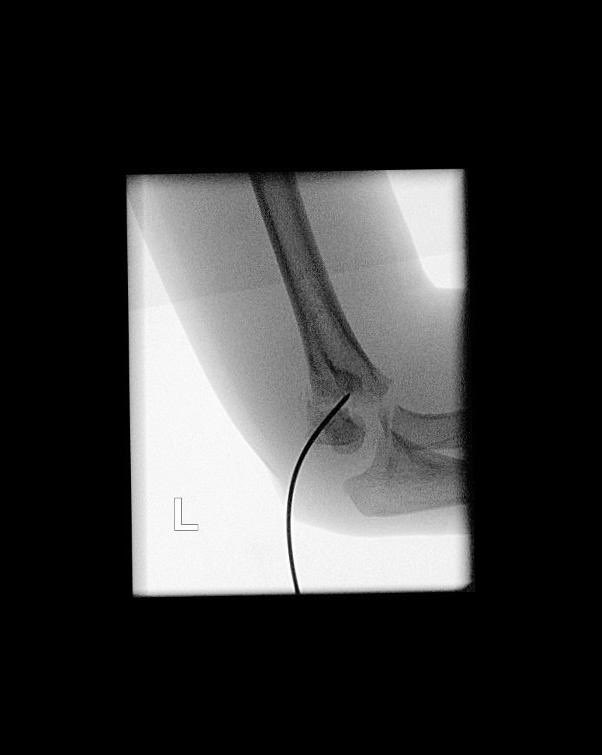

A little, flexible K-wire can do the trick! #Kapandji #BasicPhysics #LeverArm #PerCutaneousReduction #SupraCondylarFracture #MedTwitter #orthotwitter #OrthoTweetorial #SundayThoughts